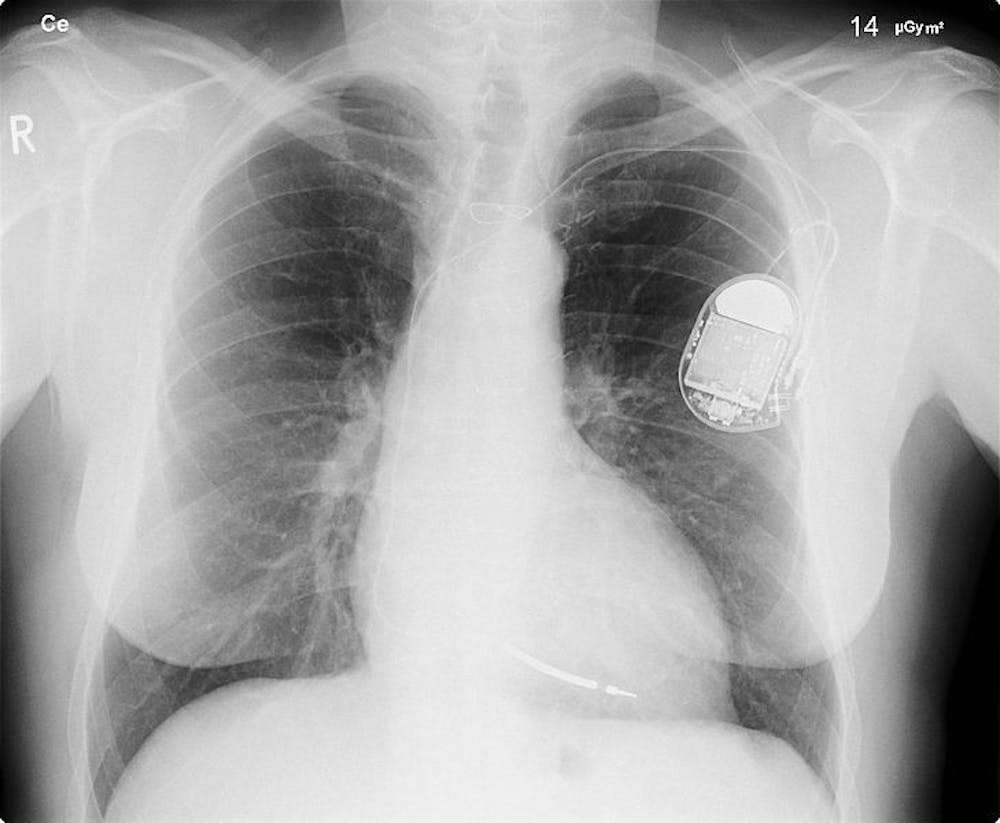

De FDA, het agentschap van de federale overheid van de Verenigde Staten dat de kwaliteit van het voedsel en de medicijnen controleert, riep in 2017 al 500 duizend pacemakers terug vanwege het risico op hacken. Hoewel de kans klein is dat hackers hier gebruik van zullen maken en er vooralsnog geen voorbeelden bekend zijn van pacemakers en insulinepompen die zijn gehackt, waarschuwen experts al geruime tijd voor dit risico. Dit was voor de voormalig Amerikaanse vicepresident Dick Cheney reden genoeg om de draadloze functie van zijn pacemaker door zijn artsen uit te laten zetten, vertelde hij in een interview met een bekend Amerikaans praatprogramma.